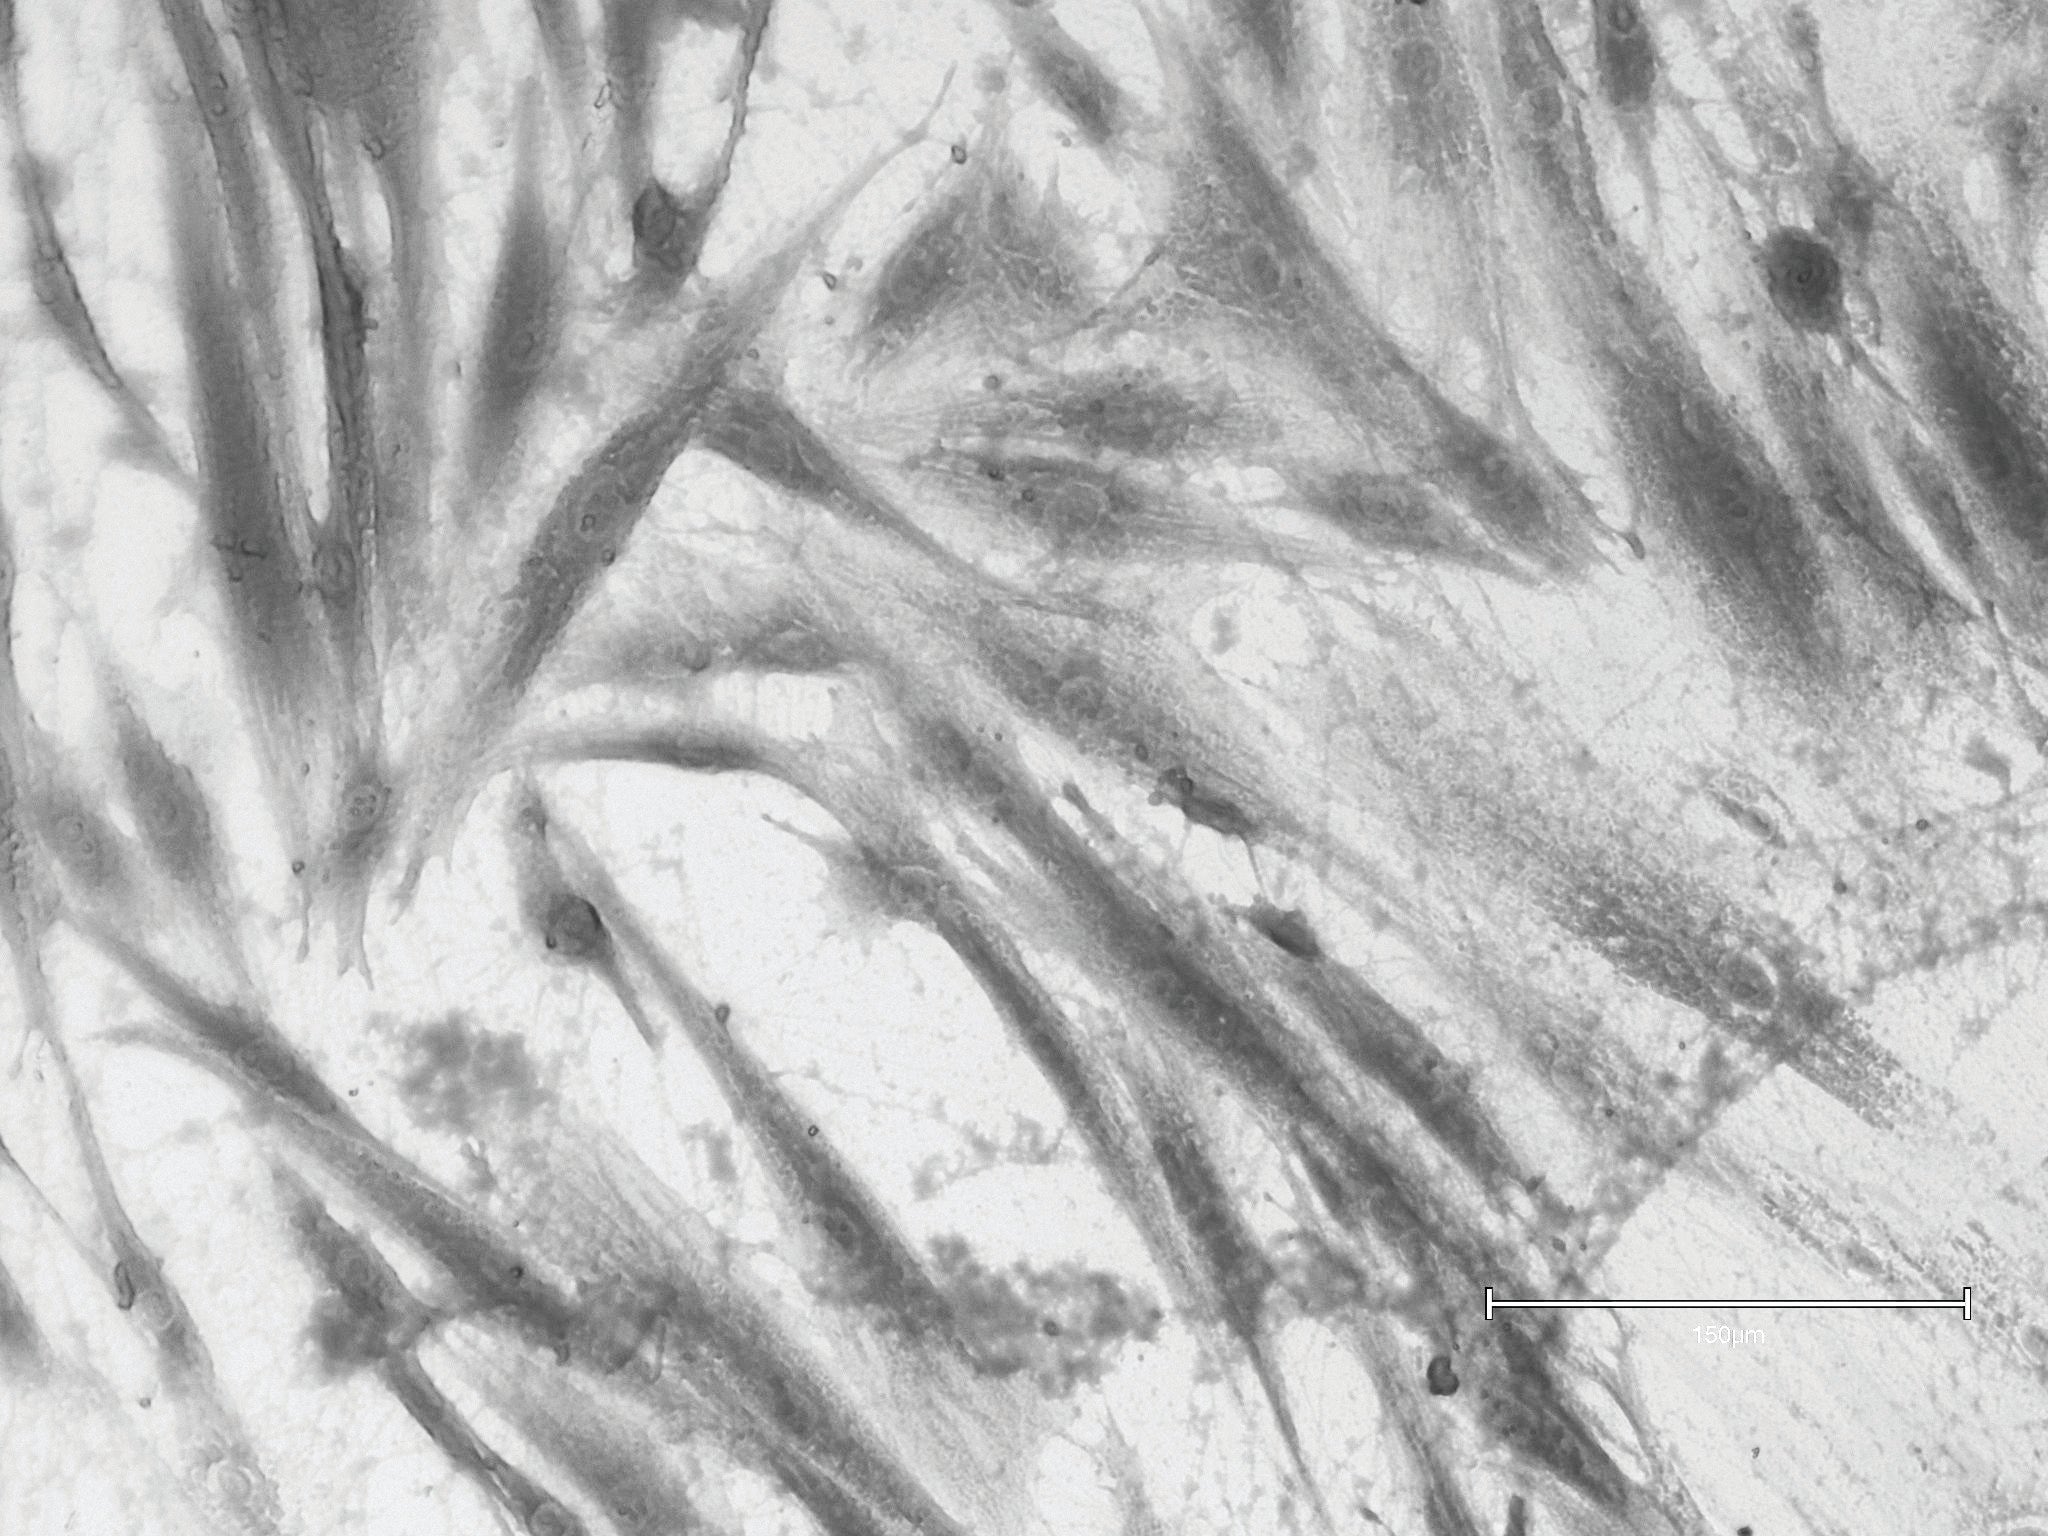

No Treatment (Control)

Cultured fibroblast from abdominal skin; fibroblast cells with reduced metabolic activity, pre-senescent phenotype, indicating exhaustion and cellular fatigue